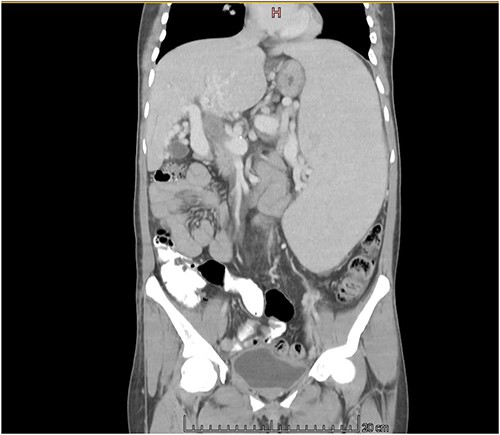

The CT scan exhibited features consistent with portal hypertension and associated changes in the pre-portal venous system, liver, and spleen (Figs 1 and 2).

CT scan coronal view showing gross hepatosplenomegaly with large collaterals suggestive of portal venous hypertension with portal biliopathy. Chronic thrombus seen in SMV and portal confluence.